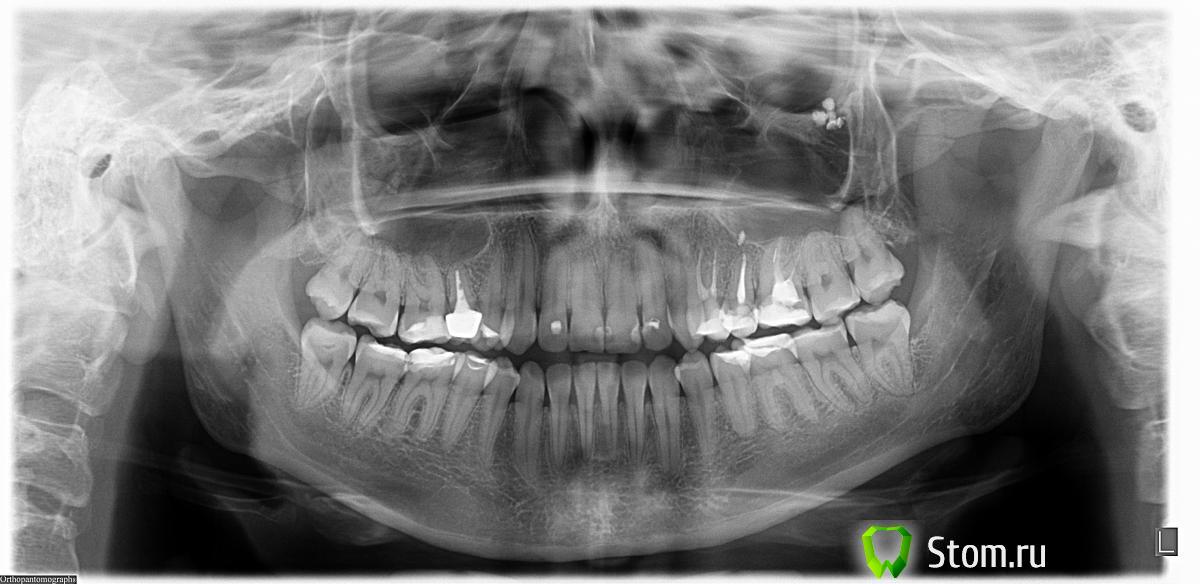

Rozettka Опубликовано 13 января, 2012 Поделиться Опубликовано 13 января, 2012 Добрый день, уважаемые стоматологи!Буду очень благодарна вашему совету. Ситуация следующая: 5 лет назад на 5 зуб сверху ставили металлокерамическую коронку (ранее на зубе был пульпит, который залечили, через некоторое время отломалась солидная часть зуба (осталось от него около 3 мм и очень тонкие стенки), что собственно и привело к поставке коронки). На выходных при удалении частиц пищи между зубами почувствовала, что коронка подалась вниз... В среду была у ортопеда.Он двумя пальцами достал коронку!!! Она была посажена не на штифт, а пломбу (если я правильно поняла адамантиновую). Пломба выпала, а соответственно с ней и коронка. Слава Богу у меня плотные зубы и коронка держалась за счет них. Зуб уже потемнел. Тут же был сделан прицельный снимок: канал плохо запломбирован, корень почти разрушен врач сказал, что есть 2 варианта: 1. Пытаться спасти зуб, при этом необходимо делать ревизию канала (распломбировать и пломбировать заново), затем штифт и на него коронку. Врач сказал, что 8 лет простоит. 2. Удалять зуб и вставлять имплантат. Я в растерянности... Боюсь неприживления имплантата и возможных проблем. Хотелось бы узнать вживляемая часть имплантата насколько надежна, не придется ли делать повторную операцию? Сегодня была у второго доктора, посоветовал удалять т.к зуб спасти вероятности практически нет. Из дальнейших вариантов только удаление и имплантация (мост на 3 зуба не рассматриваю) Сделали панорамный снимок (речь идет о правой верхней пятерке). Доктор сказал, что большая вероятность того, что кости не хватит для имплантата, необходимо добавлять. Пожалуйста, если не трудно по снимку можете посоветовать как поступить и нужна ли операция по изменению гайморитовой пазухи. Одновременно подумываю удалить левую верхнюю восьмерку (растет в сторону щека, лечили кариес на ней), только не уверена стоит ли это делать, зубы все же на разных сторонах. Заранее огромное спасибо. Ссылка на комментарий